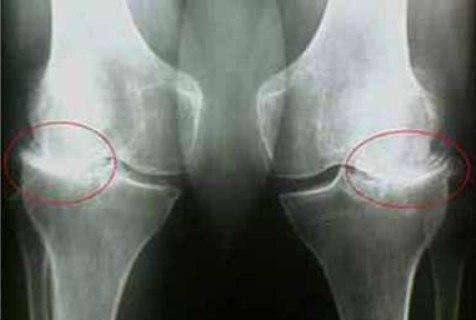

35-η

μέρα:έκανα εξετάσεις και ακτινογραφία του ώμου και του αγκώνα. Δεν υπάρχουν ίχνη αρθρώσεων! Ο

χόνδρος στις αρθρώσεις είναι σαν ενός νεαρού 30 ετών. Ο γιατρός είπε ότι στην προηγούμενη ακτινογραφία

υπήρχε πιθανότατα ένα ελάττωμα, οπότε η διάγνωση της οστεοαρθρίτιδας ήταν εσφαλμένη.